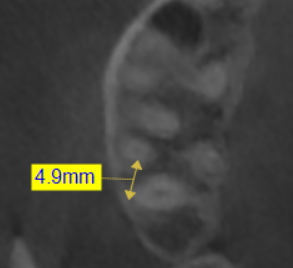

Métodos: Se llevó a cabo un caso clínico en una paciente de 40 años con fracaso de restauración fija dentosoportada en el incisivo central superior izquierdo, asociado a caries radicular subgingival con mal pronóstico restaurador. Tras la evaluación clínica y radiográfica, se indicó la exodoncia atraumática del diente afectado. Inmediatamente después, se realizó la colocación de un implante postextracción. El defecto periimplantario (gap) fue rellenado con un xenoinjerto óseo bovino. De forma simultánea, se llevó a cabo un injerto de tejido conectivo con el objetivo de optimizar el volumen y la estabilidad de los tejidos blandos periimplantarios. Se procedió a la colocación de una restauración provisional inmediata atornillada, diseñada para preservar el perfil de emergencia y guiar la cicatrización de los tejidos periimplantarios. Tras un periodo de cicatrización de cuatro meses, se colocó la restauración definitiva atornillada.

Resultados: El seguimiento clínico y radiológico evidenció una correcta osteointegración, estabilidad de los tejidos periimplantarios y un resultado estético satisfactorio, mantenido a los cuatro años.